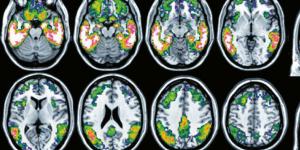

illustration : Leucémies

Leucémies : mieux détecter les rechutes

Anne-Marie Trabichet